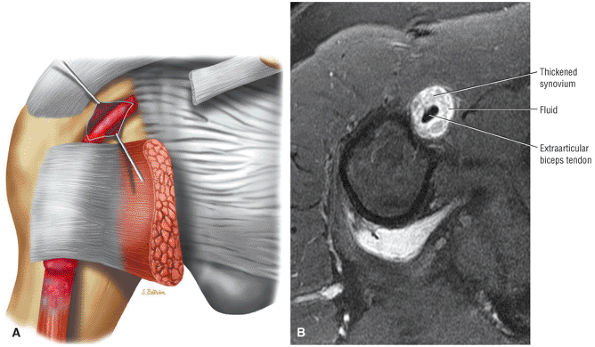

stripped from its lesser tuberosity attachment. However, because of an intact connection with the transverse humeral ligament, which connects the subscapularis tendon to the greater tuberosity, the tendon fibers appear to course in continuity without retraction. Proximal biceps tendon and subscapularis tendon pathology commonly coexist, since the pathogenesis of tendinosis and tears of both tendons are interrelated.